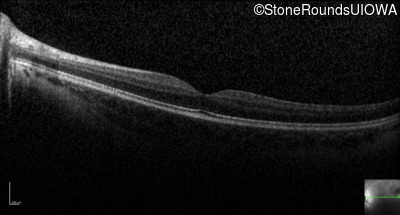

Optical Coherence Tomography - Right - 20/63 -1 sc

Exemplar / OCT Stack

OCT Stack